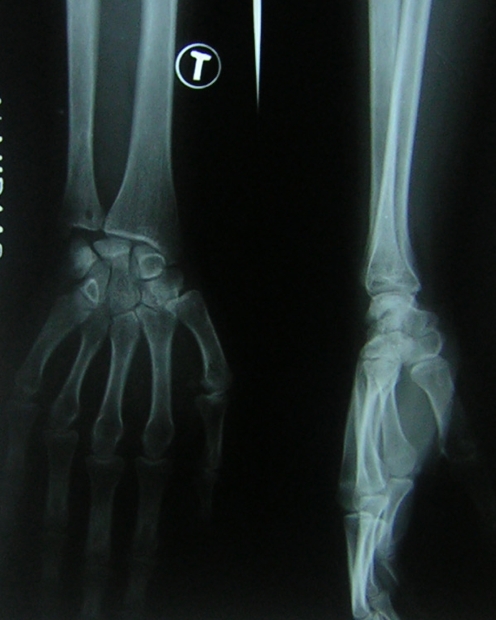

Kienbock described this lesion in 1910 and thought it was a result of trauma. He believed that repeated sprains, contusions or subluxations led to ligamentous and vascular injury resulting in a loss of blood supply to the lunate. Others have described the pathology as resembling avascular necrosis [3, 10]. It was Hulten who found a 78% incidence of a short ulna in patients with Kienbock’s disease. He coined the term ulnar minus for this discrepancy. Gelberman described a method for quantifying this variation. Since then, studies contradicting Hulten’s findings have been published; however, there is a consensus that negative ulnar variance predisposes a patient to the development of Kienbock’s disease (Fig. 1) [5, 7]. A short ulna causes increased shear forces on the ulnar side of the wrist and part of the lunate. Hoogenberg showed a shift in bone density towards the scaphoid fossa, indicating altered force transmission [12].

Fig. 1.

Negative ulnar variance with avascular necrosis of the lunate. Cyst formation is visible within the lunate